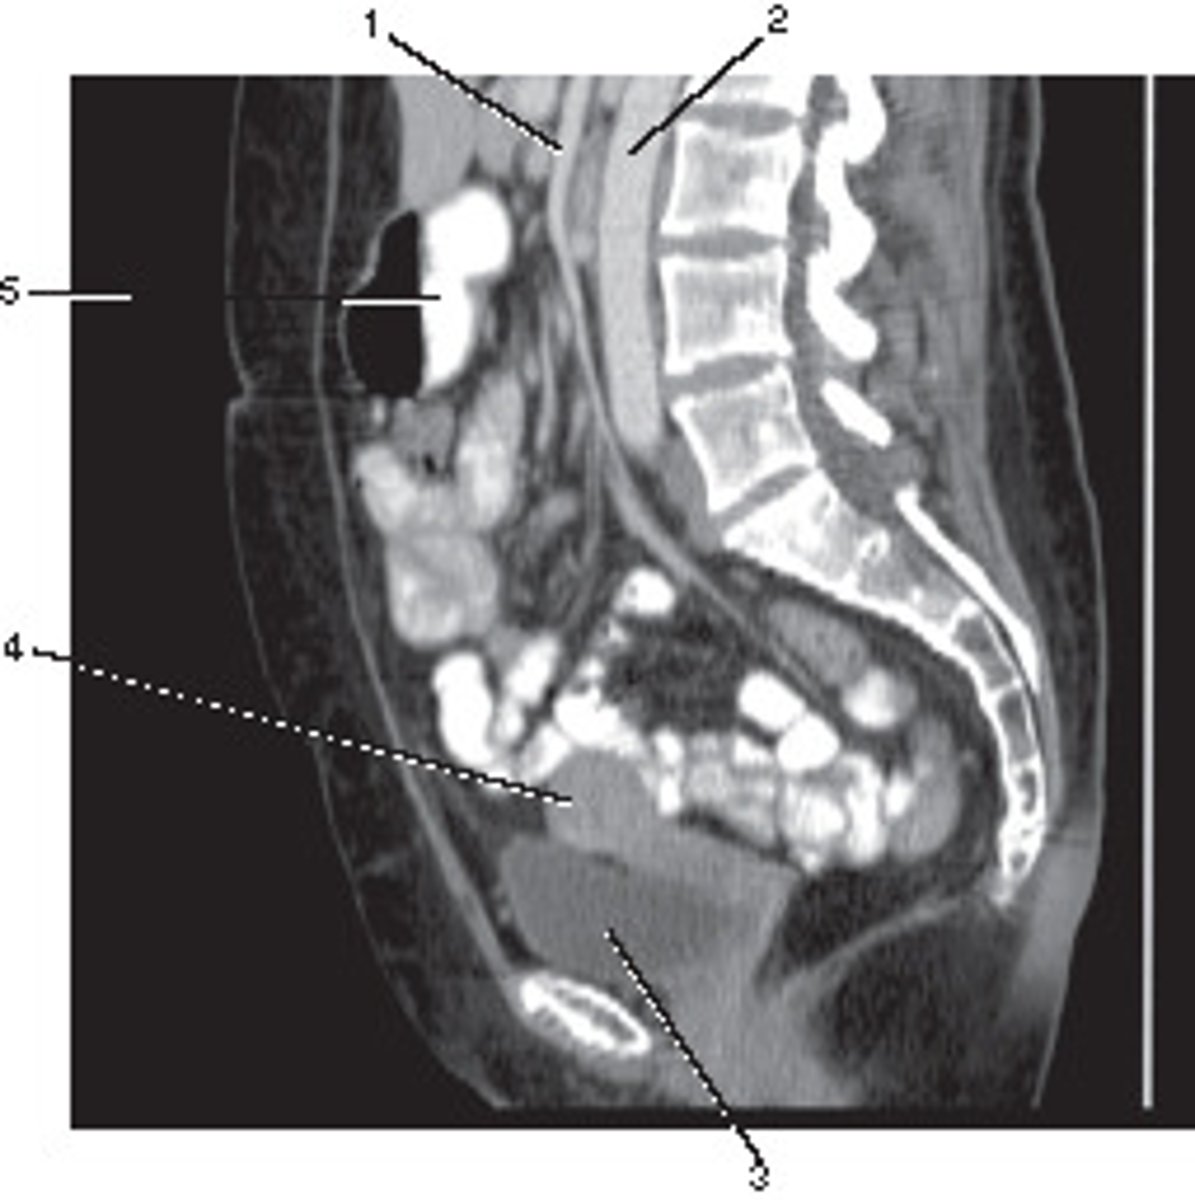

Sagittal

What anatomic plane best describes this image

<p>What anatomic plane best describes this image</p>

Ileum

Number 1 corresponds to which of the following?

<p>Number 1 corresponds to which of the following?</p>

Uterus

Number 4 corresponds to which of the following?

<p>Number 4 corresponds to which of the following?</p>

Coccyx